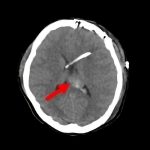

断層撮影

手術前1